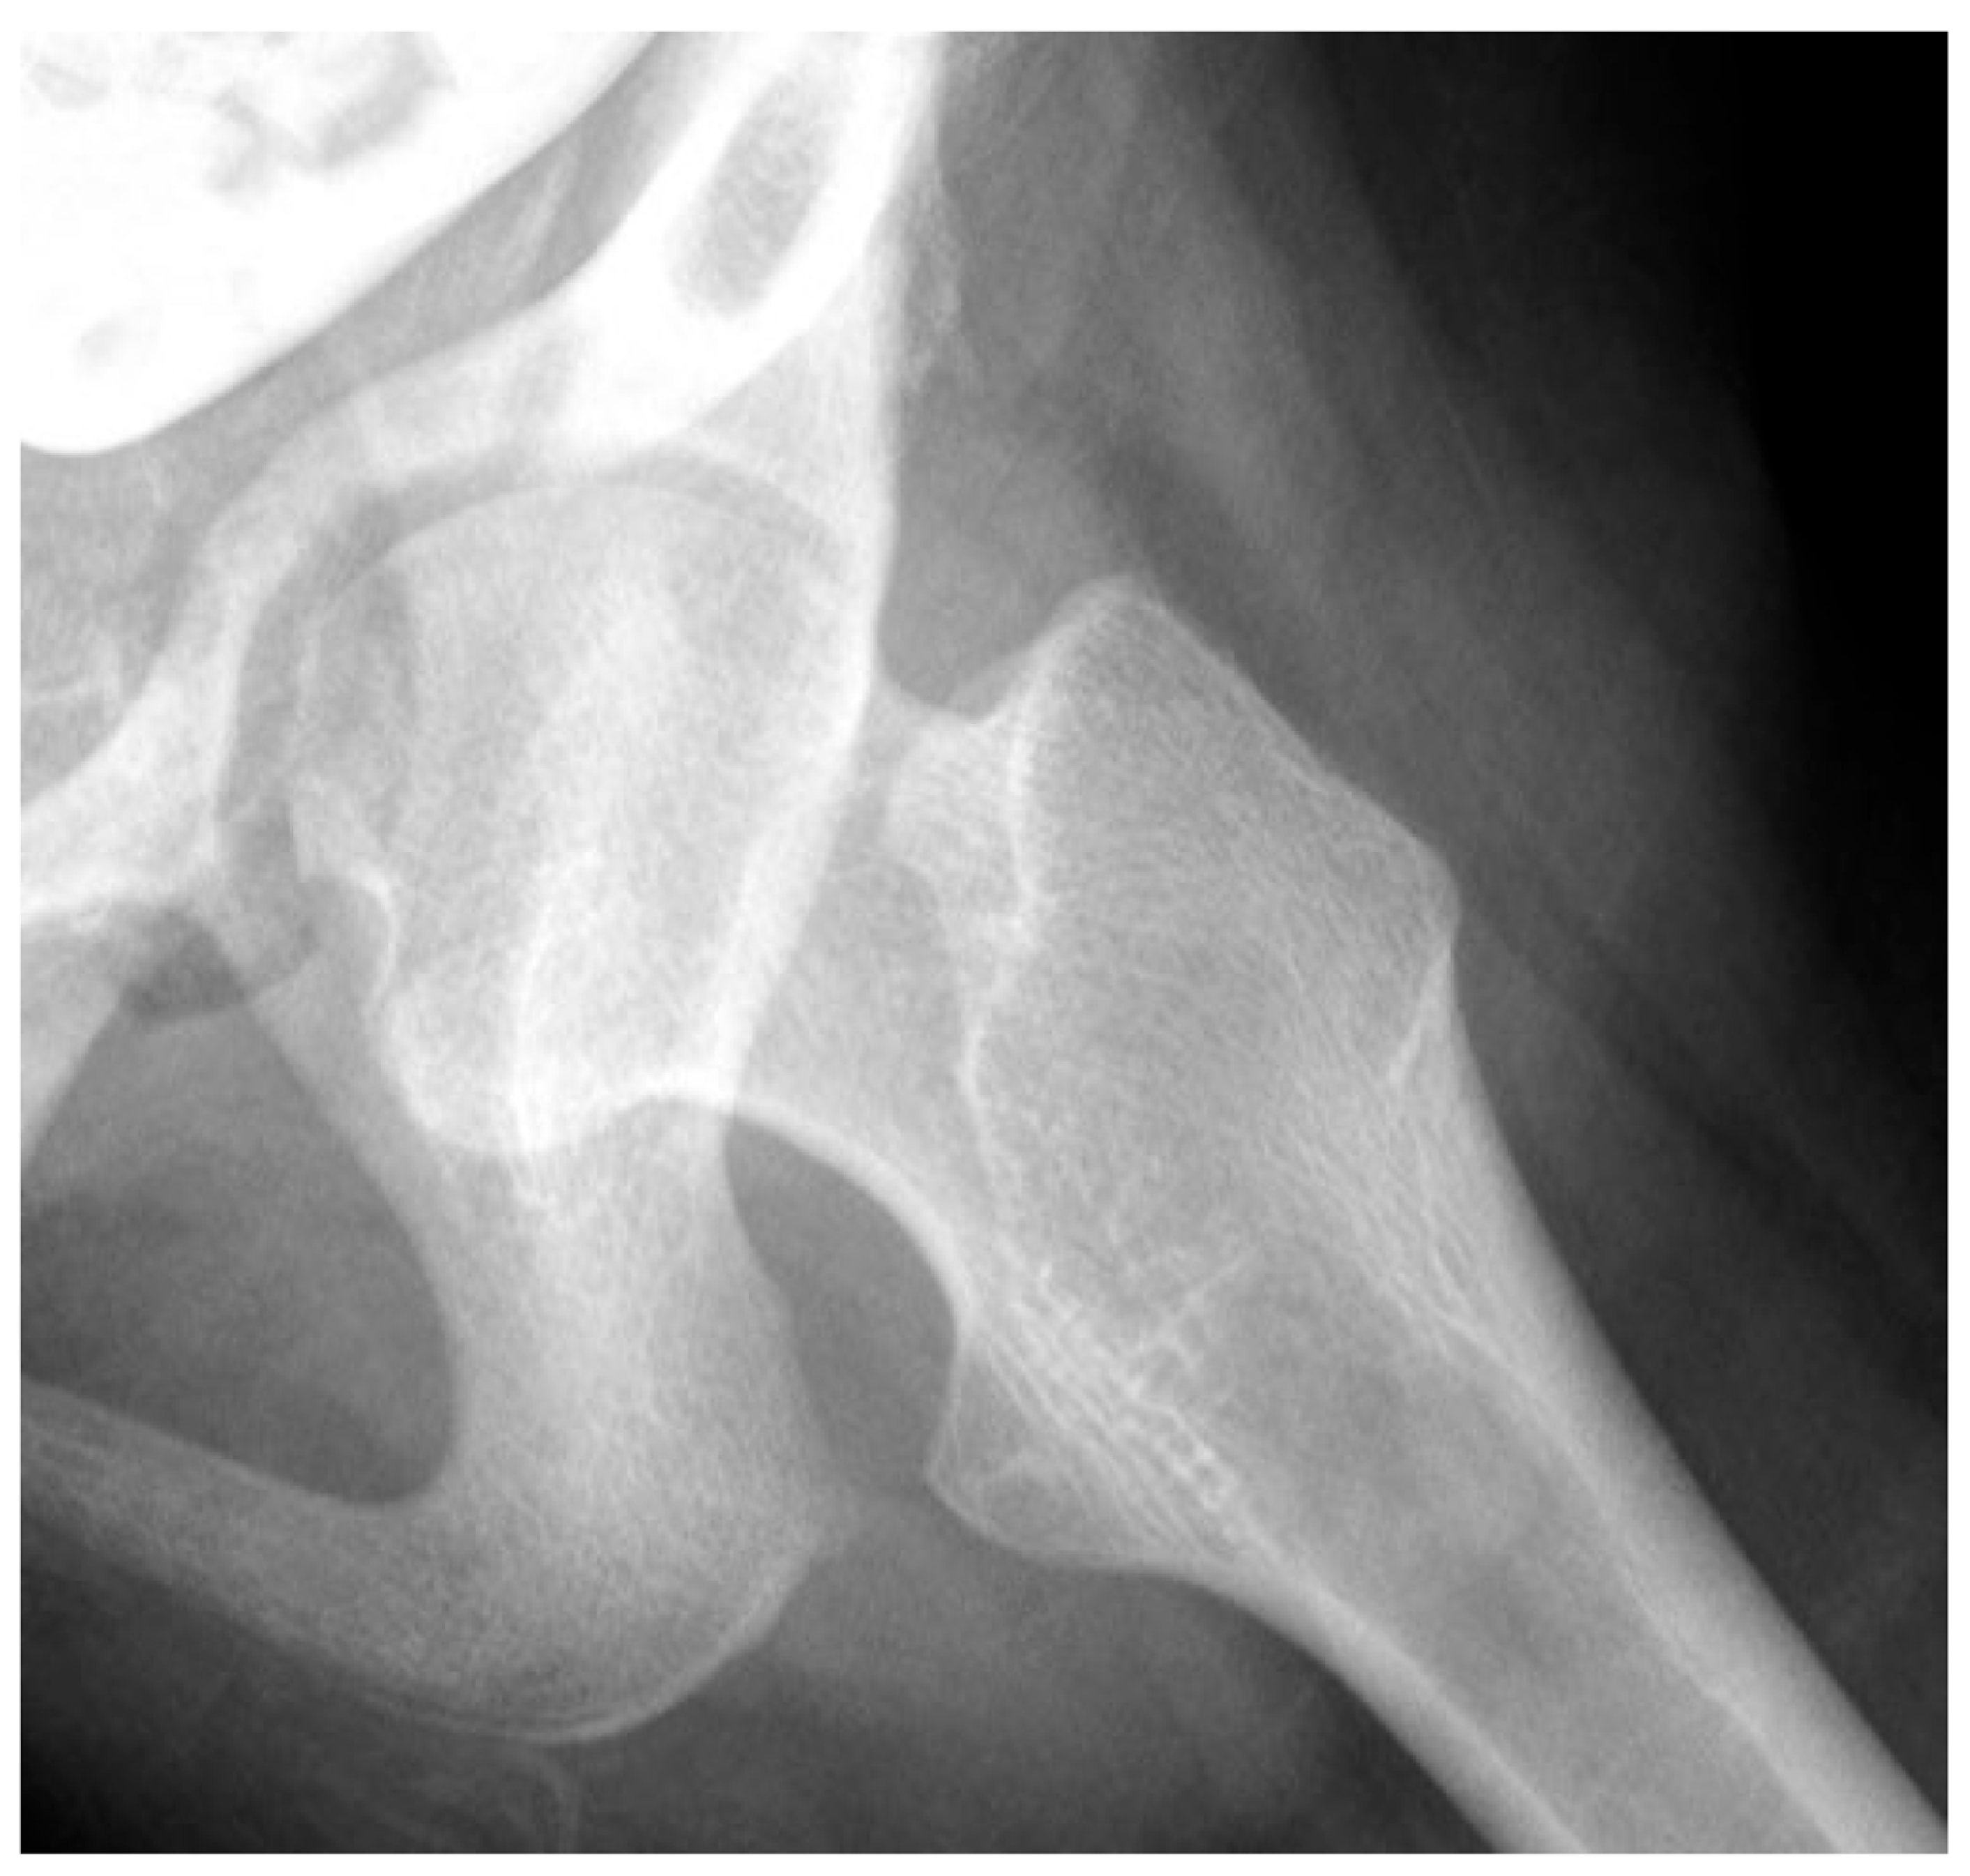

3.3.2. Pathology of Hip Development in Nonambulatory Children

3.3.3. Pathology of Hip Development in Children with Low Tone and Muscle Weakness

3.4. Femoral Factors Influencing Hip Pathology